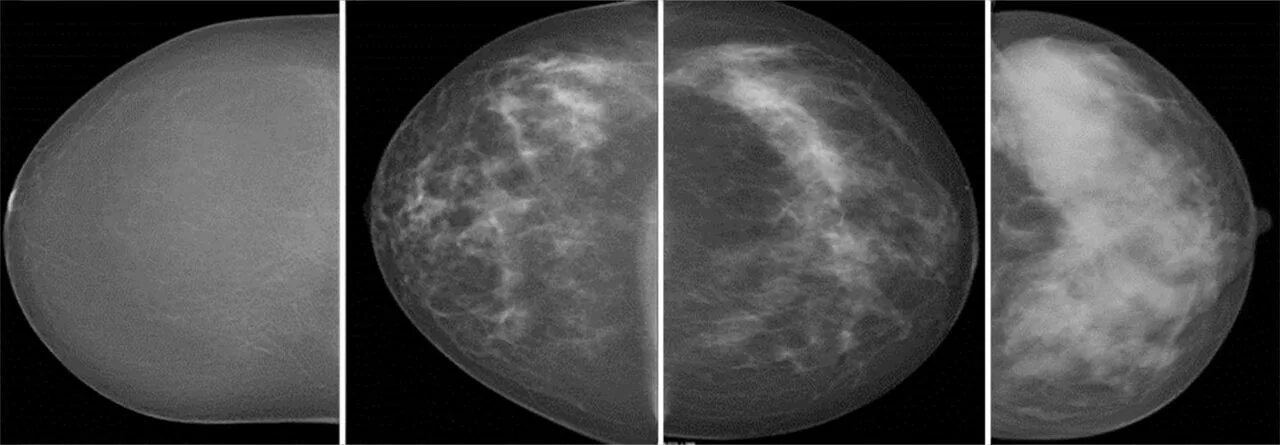

Метастазы в молочной железе прогноз